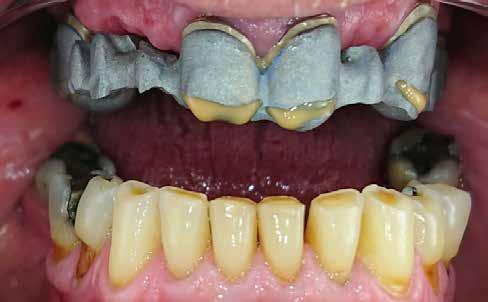

1077 Budapest, Izabella u. 10. Tel.: 06-1-223-3999, info: 06-30/944-1441 www.dentaldiszkont.hu

eszközök és anyagok a legnagyobb választékban, a legkedvezőbb áron. Raktárról azonnal szállítunk. Viszonteladóknak nagy kedvezmények.

Turn static files into dynamic content formats.

Create a flipbook

Issuu converts static files into: digital portfolios, online yearbooks, online catalogs, digital photo albums and more. Sign up and create your flipbook.